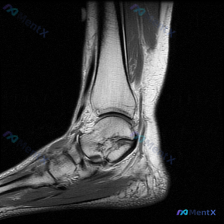

看到这个踝关节MRI的病例,整理了一下影像资料和分析思路,分享给大家讨论。 病例影像基本信息 本次提供的是踝关节水平MRI T2序列轴位图像,影像观察结果如下: 1. 骨骼结构:胫骨远端、腓骨远端、距骨穹窿骨皮质轮廓完整,无明显骨折线或显著骨髓信号异常 2. 踝关节间隙:可见少量液性信号,提示存在少...